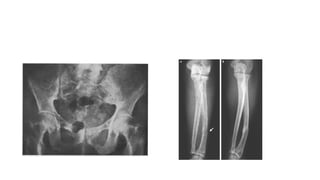

Xray findings

• Early findings consist of generalized deossification.

• The trabeculae become thinned out and disappear and cortices are

narrowed

• As disease progresses, cysts appear throughout skeleton, bending

deformities develop and renal calculi are observed.

Xray findings • Earlyfindings consist of generalized deossification. • The trabeculae become thinned out and disappear and cortices are narrowed • As disease progresses, cysts appear throughout skeleton, bending deformities develop and renal calculi are observed. • Skull displays diffuse osteoporosis – ‘Pinhead Stippling’ • Vertebrae are porotic and deeply indented by ballooned discs. Collapse is frequent. ‘Rugger Jersey spine’ • Dental films reveal dimineralization of mandible and disappearance of lamina dura and epulis tumors